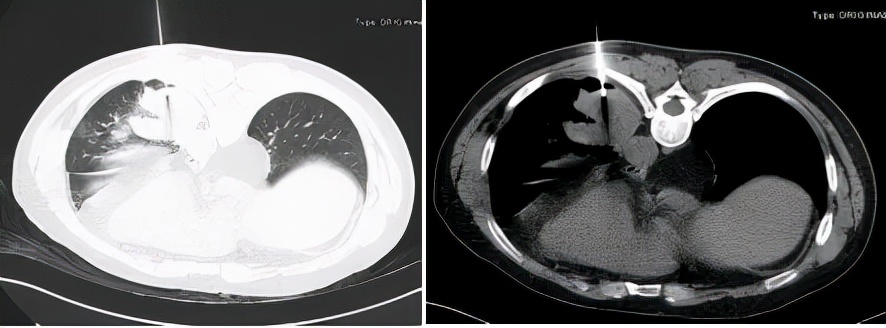

2020年4月28日胸部增强CT:1、左肺下叶后基底段见不规则团片影,较大层面约6.4×5.1cm,其内见少许点状钙化灶,增强后轻度强化,周围见斑片、条索影,邻近胸膜增厚、黏连。2、右肺中叶、左肺下叶、左侧斜裂小结节,较大者约0.4cm,多系炎性。3、双肺少许慢性炎症。4、心脏未见增大,肺动脉干稍增粗。5、左肺门淋巴结稍大。6、食管裂孔疝(图4及图5)。

图4:胸部增强CT(2020年4月28日)

图5:胸部增强CT纵隔窗(2020年4月28日)

2020年4月30日支气管镜检查:各级支气管粘膜光滑,通畅,未见异常(图6)。

图6:支气管镜下改变

BALF:送检TB-XPERT, GM试验,细菌和真菌培养均阴性。

2020年5月2日胸部CT:第二次经皮肺穿刺活检(图7),并抽出液化区血性液体(图8)。

图7:第二次经皮肺穿(2020-5-2)

图8:经皮肺穿刺抽出血性液体(2020-5-2)

病理诊断为:肺组织慢性炎,局灶纤维组织增生,慢性炎细胞聚集。穿刺液完善NGS及培养均查见曲霉菌。